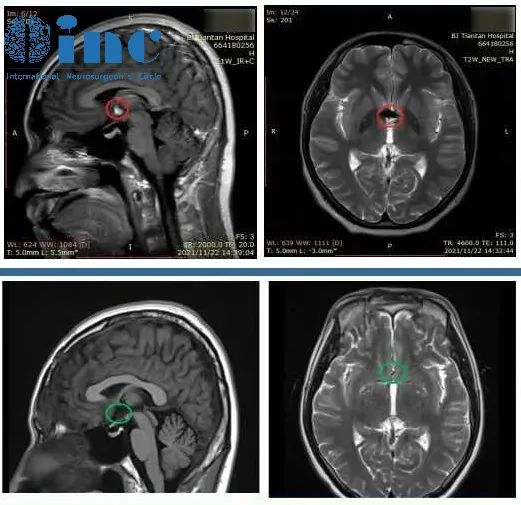

以下还有INC德国巴特朗菲教授三脑室海绵状血管瘤案例交流:

病情回顾:26岁的浩然是一名大学在读研究生,在一次暑假西藏旅游归来后,开始频繁出现头痛、头晕的情况。起初以为是离开高原后的“醉氧”反应,休息几天就好了,但是没想到头痛头晕的症状一直没有好转,甚至在旅游回家两个月后依然存在,并且和普通头晕头痛不同,浩然头痛头晕还伴着坐下站立的一瞬间,头后部及尾椎部同步疼痛,甚至有时候站立不稳。头颅核磁检查后考虑三脑室海绵状血管瘤。

治疗过程:远程咨询INC德国巴教授,巴教授表示“可以手术,可以全切全切,手术风险很低”;春节前夕赴德国INI接受巴教授手术,额底形成开颅术,广开额窦,经大脑纵裂额底入路的显微外科血管畸形全切术,术中成功顺利全切肿瘤,在电生理监测下无新发神经损伤,无术中、术后并发症。